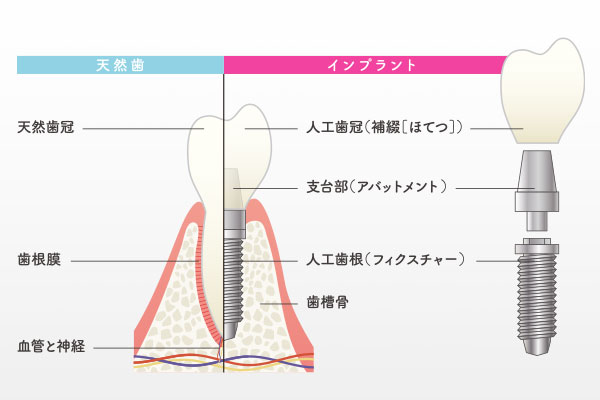

インプラント治療は、失った歯を補うために人工の歯根(歯の根っこ)をあごの骨に埋め込む治療法です。インプラント体は通常チタンでできており、チタンが骨と結合する性質があることから、強固で安定した基盤が作られ、その上にアバットメント(土台)を接続し、上部構造(人工歯)を装着します。これにより、見た目も自然で、機能的にも快適な歯を再建することができます。インプラントは自分の歯とほぼ同じように感じられ、他の歯への負担も最小限に抑えられます。